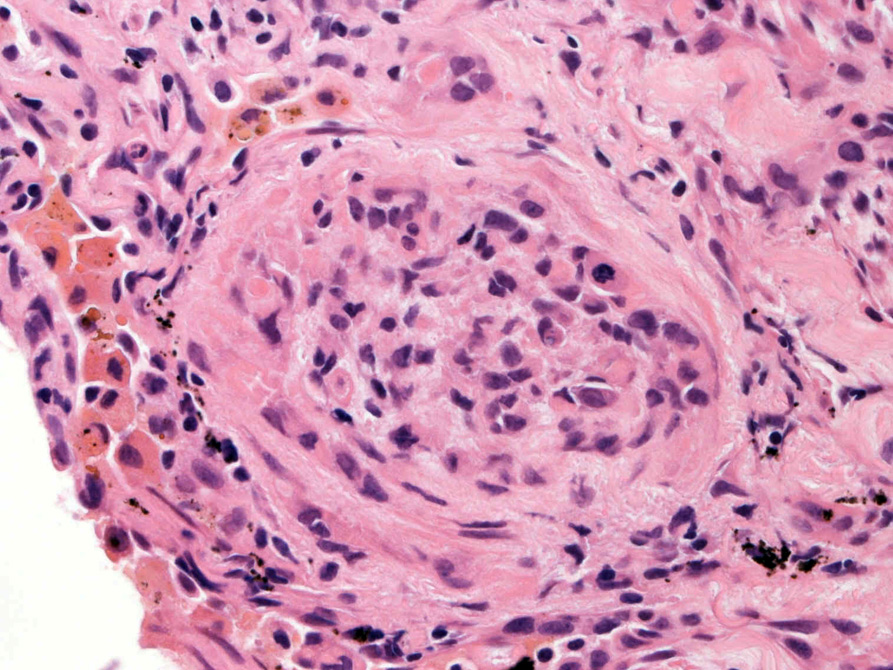

直径5-6mmの, 中央に弾性線維をふくむfibrous noduleがあり, 腫瘍細胞は結節の辺縁部に沿って認められる。

hyperchromaticな類円ないし多角の核で好酸性の広めの細胞質をもつ上皮様細胞が増殖している。右図では血管内を占拠するように腫瘍細胞が認められる。